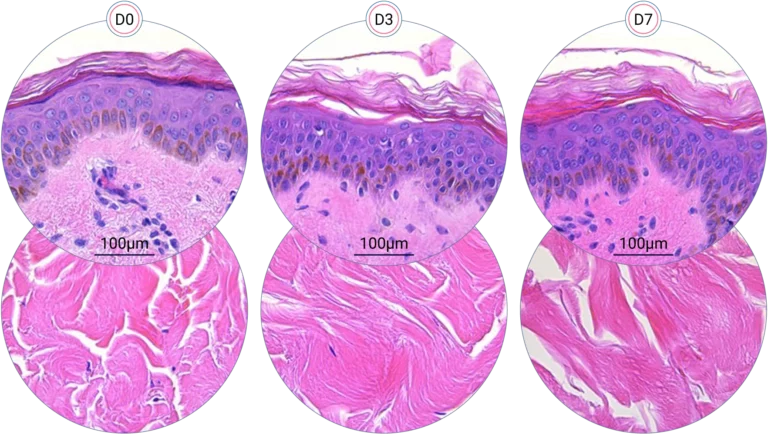

Human skin structure is maintained for +7 days

Since it is real human skin, NativeSkin® has the same structure and composition as in vivo human skin. It presents a mature stratum corneum and normal skin barrier function and their integrity can be preserved for 7 days. After 7 days of culture, experimental data may show higher variability but NativeSkin® remains viable. Hematoxilin & Eosin staining shows mature stratum corneum, a dermal-epidermal junction that comprises the key features of the dermal-epidermal junction of real human skin, with a preserved basal layer and rete ridges. The images also illustrate that dermis integrity is preserved for 7 days.